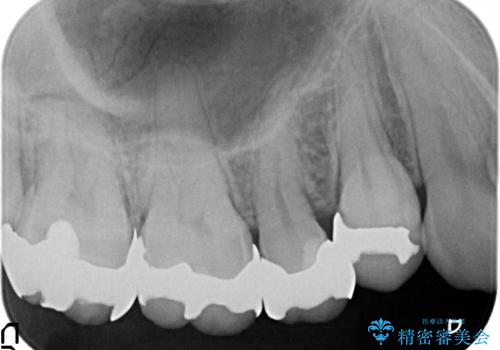

- 頬側から見たとき右上5番目の銀歯が気になるので、オールセラミッククラウンによる補綴を行った症例です。